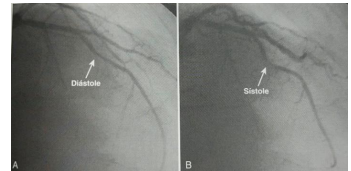

Uma mulher de 45 anos, previamente hígida, apresenta dor anginosa típica, sendo submetida a cineangiocoronariografia, que produz a seguinte imagem:

Fonte: Braunwald – Tratado de Doenças Cardiovasculares – 9ª edição

Dentre as opções abaixo, a que apresenta, respectivamente, a melhor opção terapêutica e a artéria acometida no caso apresentado é: